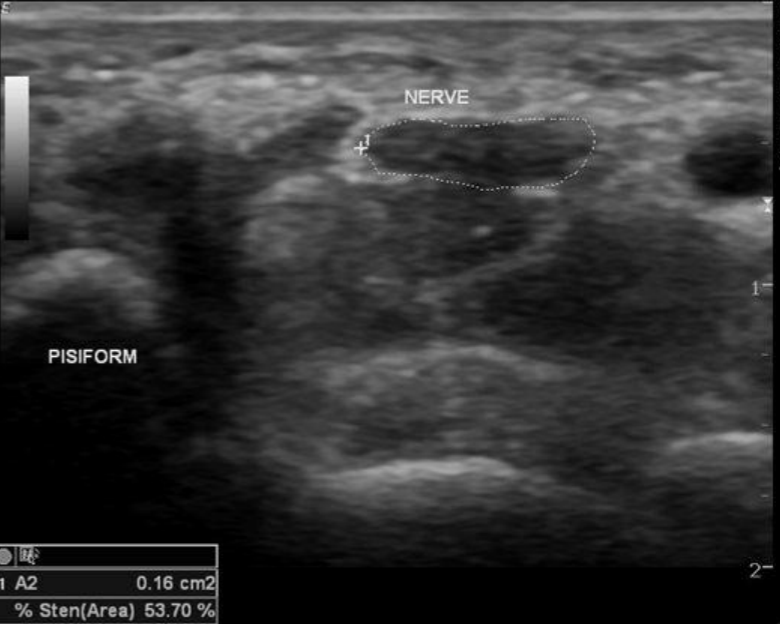

US en Sx del Tunel del Carpo

Engrosamiento del retinaculo

Aplanamiento del nervio –>Hipoecogenico